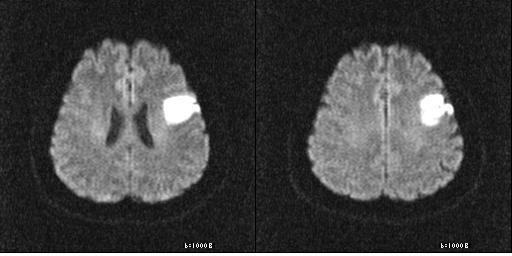

먼저, 뇌경색이 무엇인지에 대해 간단히 설명드리겠습니다. 뇌경색은 뇌에 공급되는 혈액이 차단되어 뇌세포가 손상되는 상태를 의미합니다. 대개 두 가지 종류가 있으며, 하나는 혈전으로 인한 허혈 뇌경색이고, 다른 하나는 출혈로 인한 뇌출혈입니다. 이 두 가지 모두 뇌에 큰 영향을 미치며, 생명을 위협할 수 있는 심각한 질환입니다.